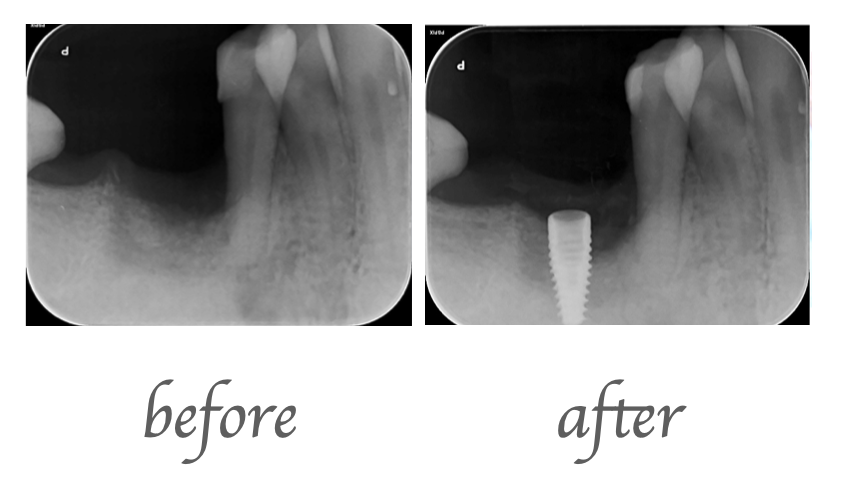

- インプラント治療によって隣の歯を残すことが出来ました。